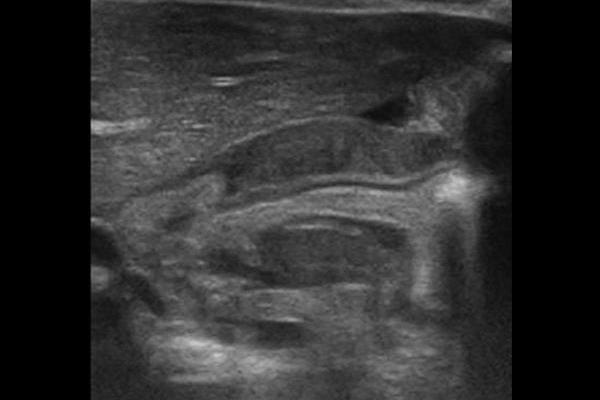

Normal Pylorus